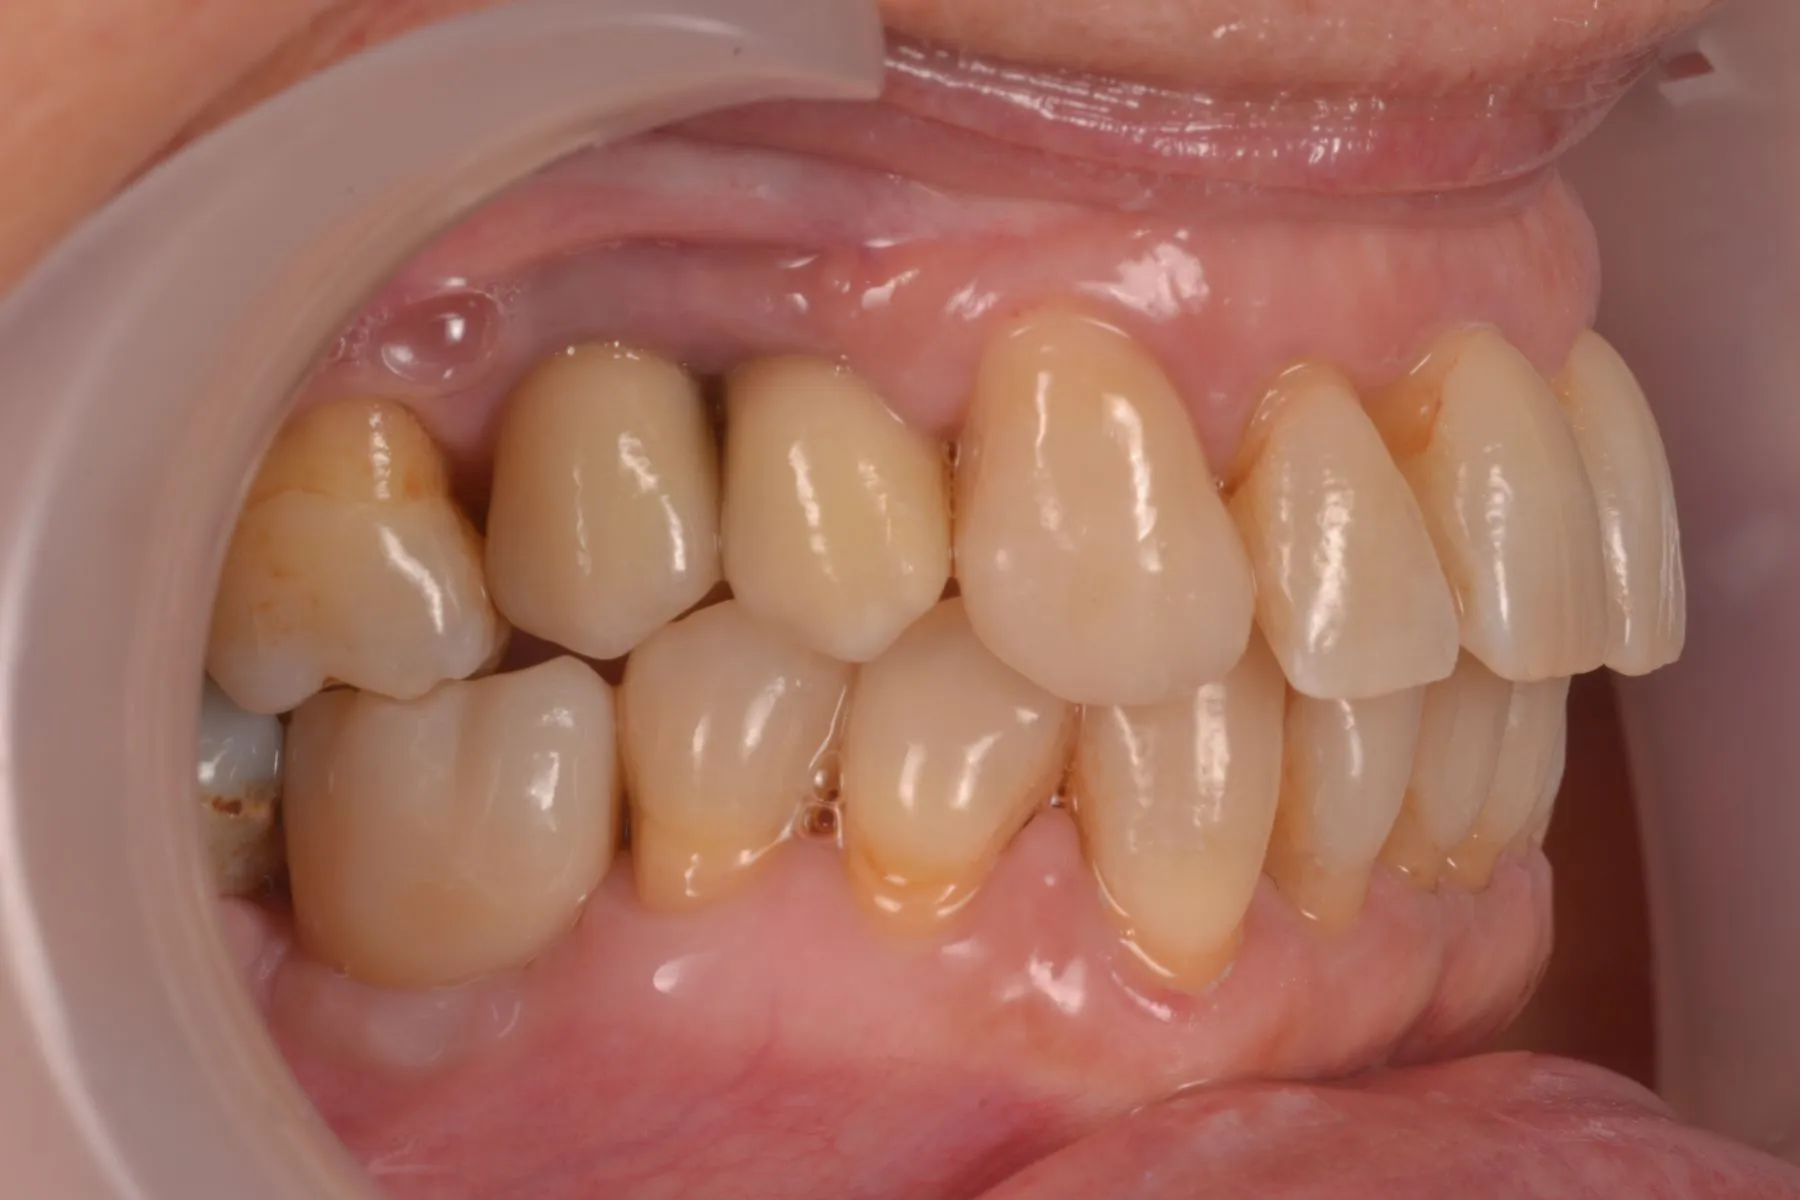

Non è una terapia chirurgica (trattamento effettuato senza eseguire tagli e senza mettere punti)

Velocità di guarigione maggiori rispetto alle terapie classiche (miglioramenti visibili dopo 2 giorni)

Non si lima e non si devitalizza il dente, mantenendo così il tuo sorriso completamente naturale

È una trattamento che si svolge in un’unica seduta atto a sanare il cavo orale riducendo la carica batterica